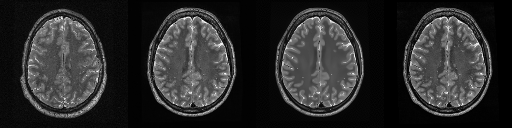

HCP T2w dataset

We utilize images from the publicly available Human Connectome Project (HCP) [51] T2-weighted (T2w) images dataset for the task of compressed sensing, which contains brain images from 47 patients. The HCP dataset includes cross-sectional images of the brain taken at different levels and angles.

Compressed sensing

We train a flow-based model from scratch on 10,000 randomly sampled images, utilizing the ncsnpp architecture [9] with minor adaptations for grayscale images. We employ compression rates , meaning . The measurement operator is given by a subsampled Fourier matrix, whose sign patterns are randomly selected. We evaluate our reconstruction algorithm’s performance on 200 randomly sampled test images.

We present the quantitative and qualitative results of compressed sensing in Tab. 1 and Fig. 4, respectively. As shown in Tab. 1, our method consistently achieves the best performance across varying compression rates . In Fig. 4, our method produces reconstructions that are more faithful to the original images, with fewer artifacts, leading to higher accuracy and clearer details.